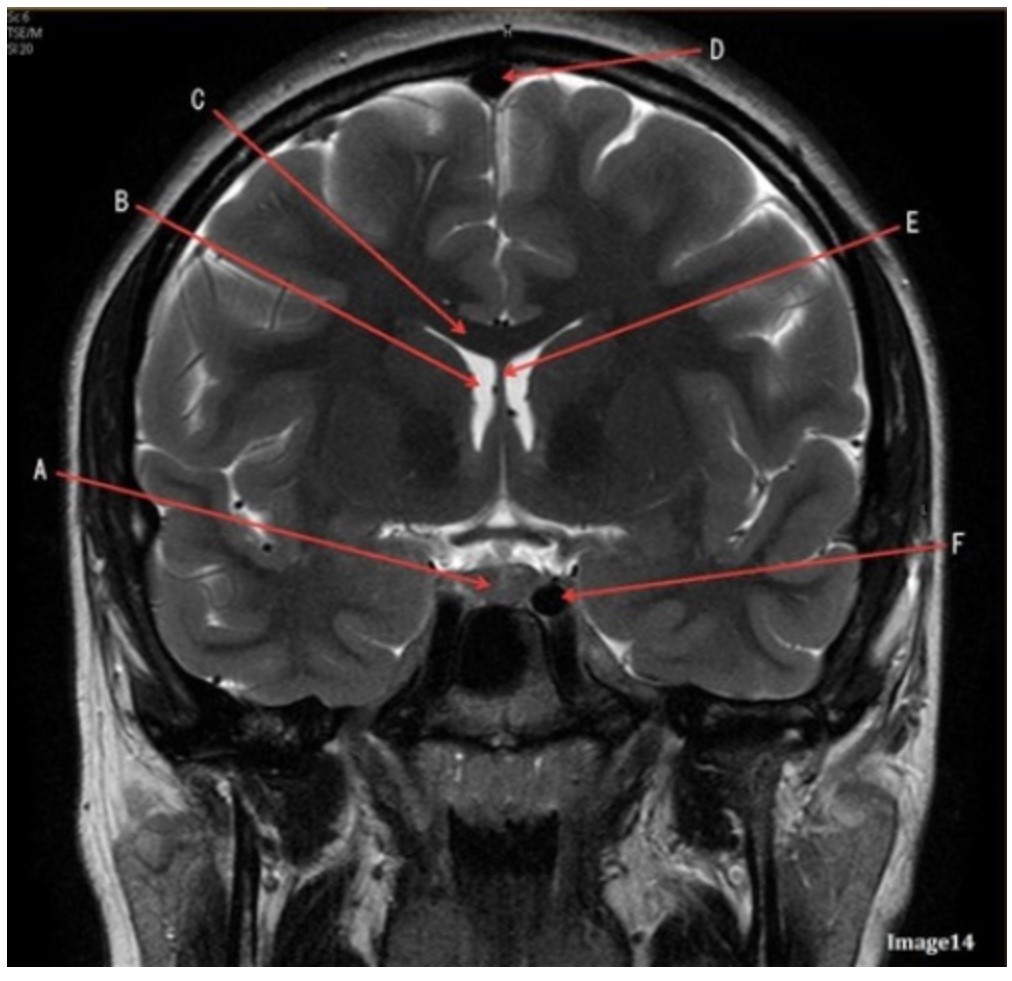

Letter F in Image 14 is pointing to:

A. Third ventricle

B. Pituitary gland

C. Hypothalamus

D. Internal carotid artery

Letter C in Image 14 is pointing to:

A. Corpus callosum

B. Third ventricle

C. Lateral ventricle

D. Pituitary gland

E. Fornix

Letter D in Image 14 is pointing to:

A. Tentorium

B. Sphenoid sinus

C. Frontal sinus

D. Sagittal sinus

E. Fornix

Letter B in Image 14 is pointing to:

A. Corpus callosum

B. Third ventricle

C. Lateral ventricle

D. Pituitary gland

E. Fornix

Letter E in Image 14 is pointing to:

A. Corpus callosum

B. Third ventricle

C. Lateral ventricle

D. Internal carotid artery

E. Fornix

Letter A in Image 14 is pointing to:

A. Corpus callosum

B. Third ventricle

C. Lateral ventricle

D. Pituitary gland

E. Fornix

Letter A in Image 14 is pointing to:

A. Corpus callosum

B. Third ventricle

C. Lateral ventricle

D. Pituitary gland

E. Fornix